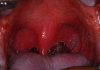

Weight loss (42%) and mucositis (42%) were the most two common moderate to severe acute toxicities that was found in this protocol. Severity of mucositis was demonstrated in Figure 2 and 3. Myelosuppression occurred subsequently, including leukopenia (30%), neutropenia (20%), anemia (12%) and thrombocytopenia (6%). Only 8% of patients had moderate to severe nausea and vomiting and no patients had renal or electrolyte abnormalities from this treatment. (Table 2)

Figure 3 Thumb

Figure 3. Grade 3 mucositis, confluent pseudomembanous mucosa.